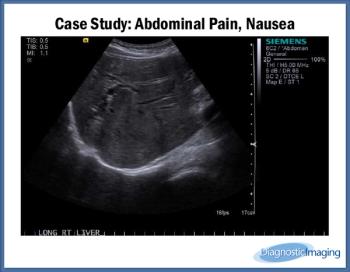

Abdominal Pain, Nausea

Case History: Female patient in early 60s with abdominal pain and nausea.